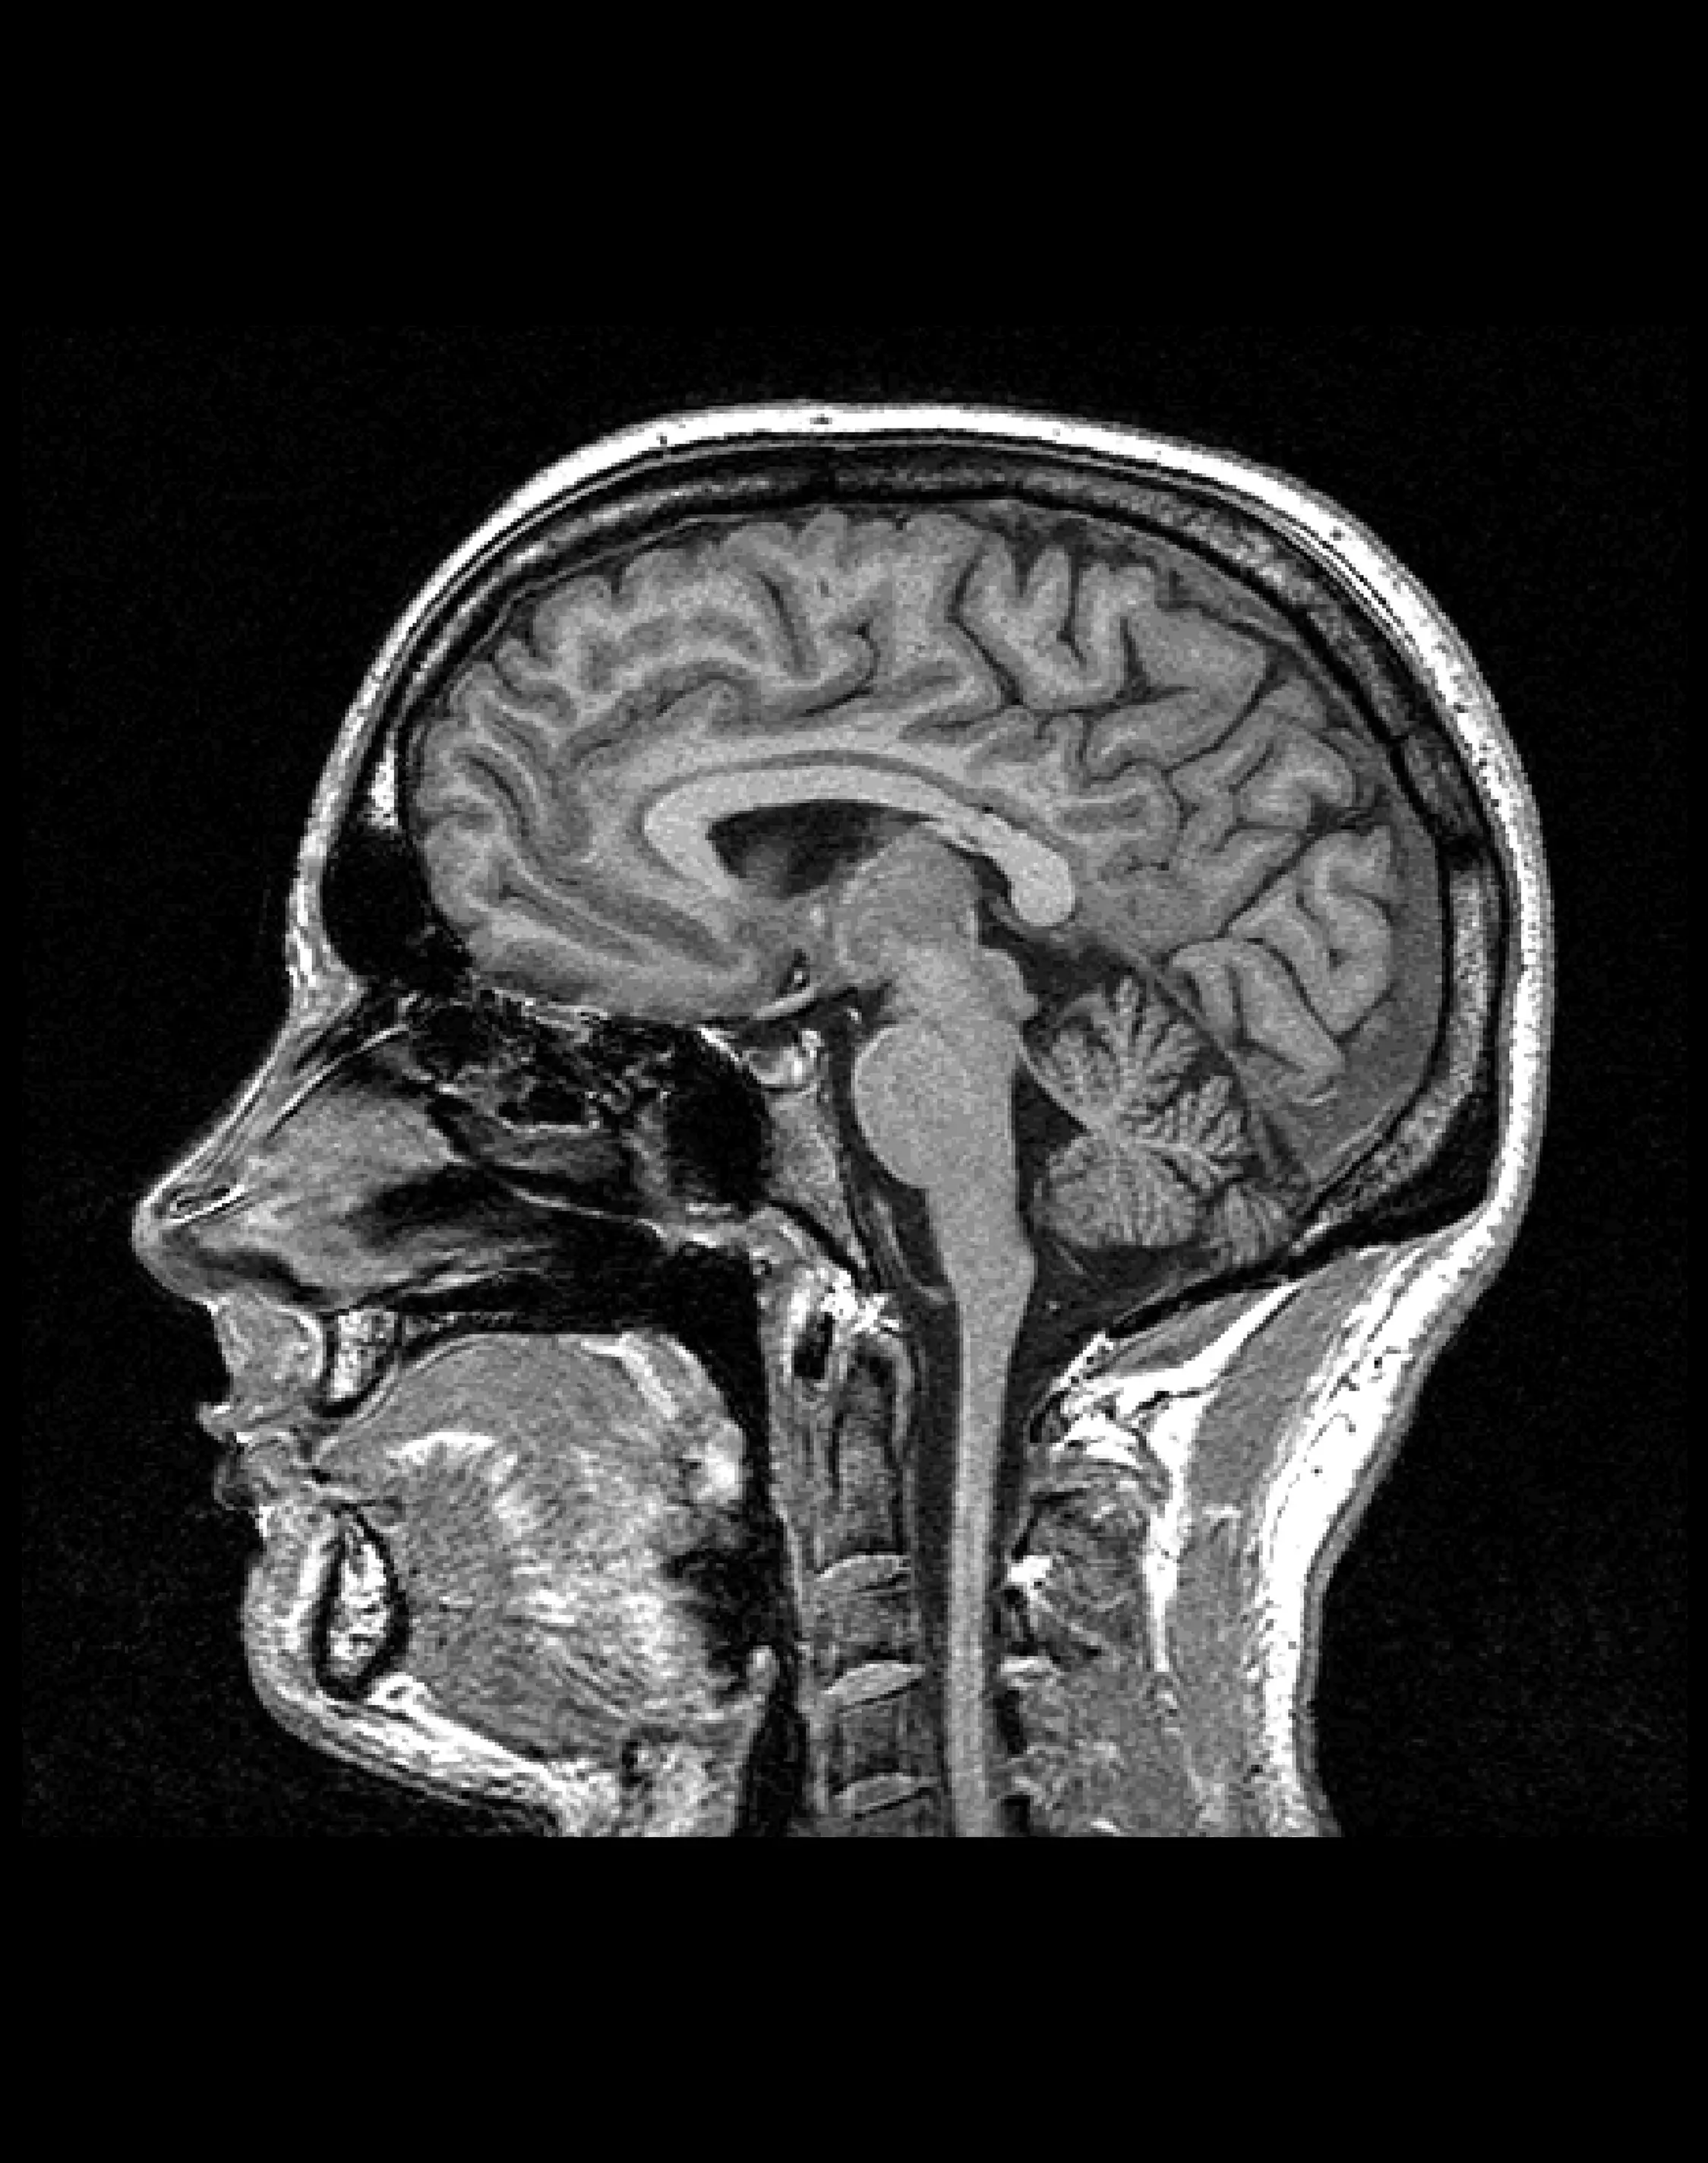

МРТ головного мозга (стандартное)